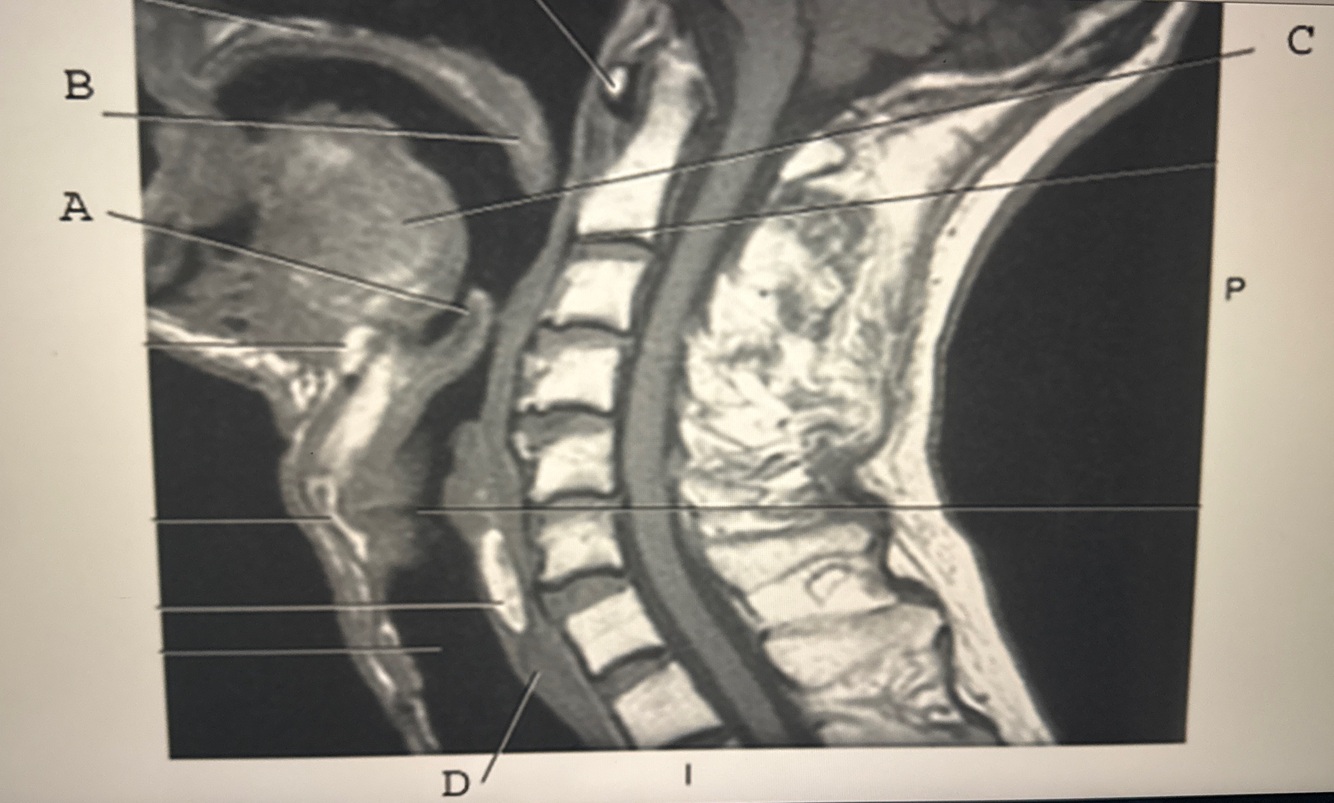

Which line points to the annulus fibrosis?

A